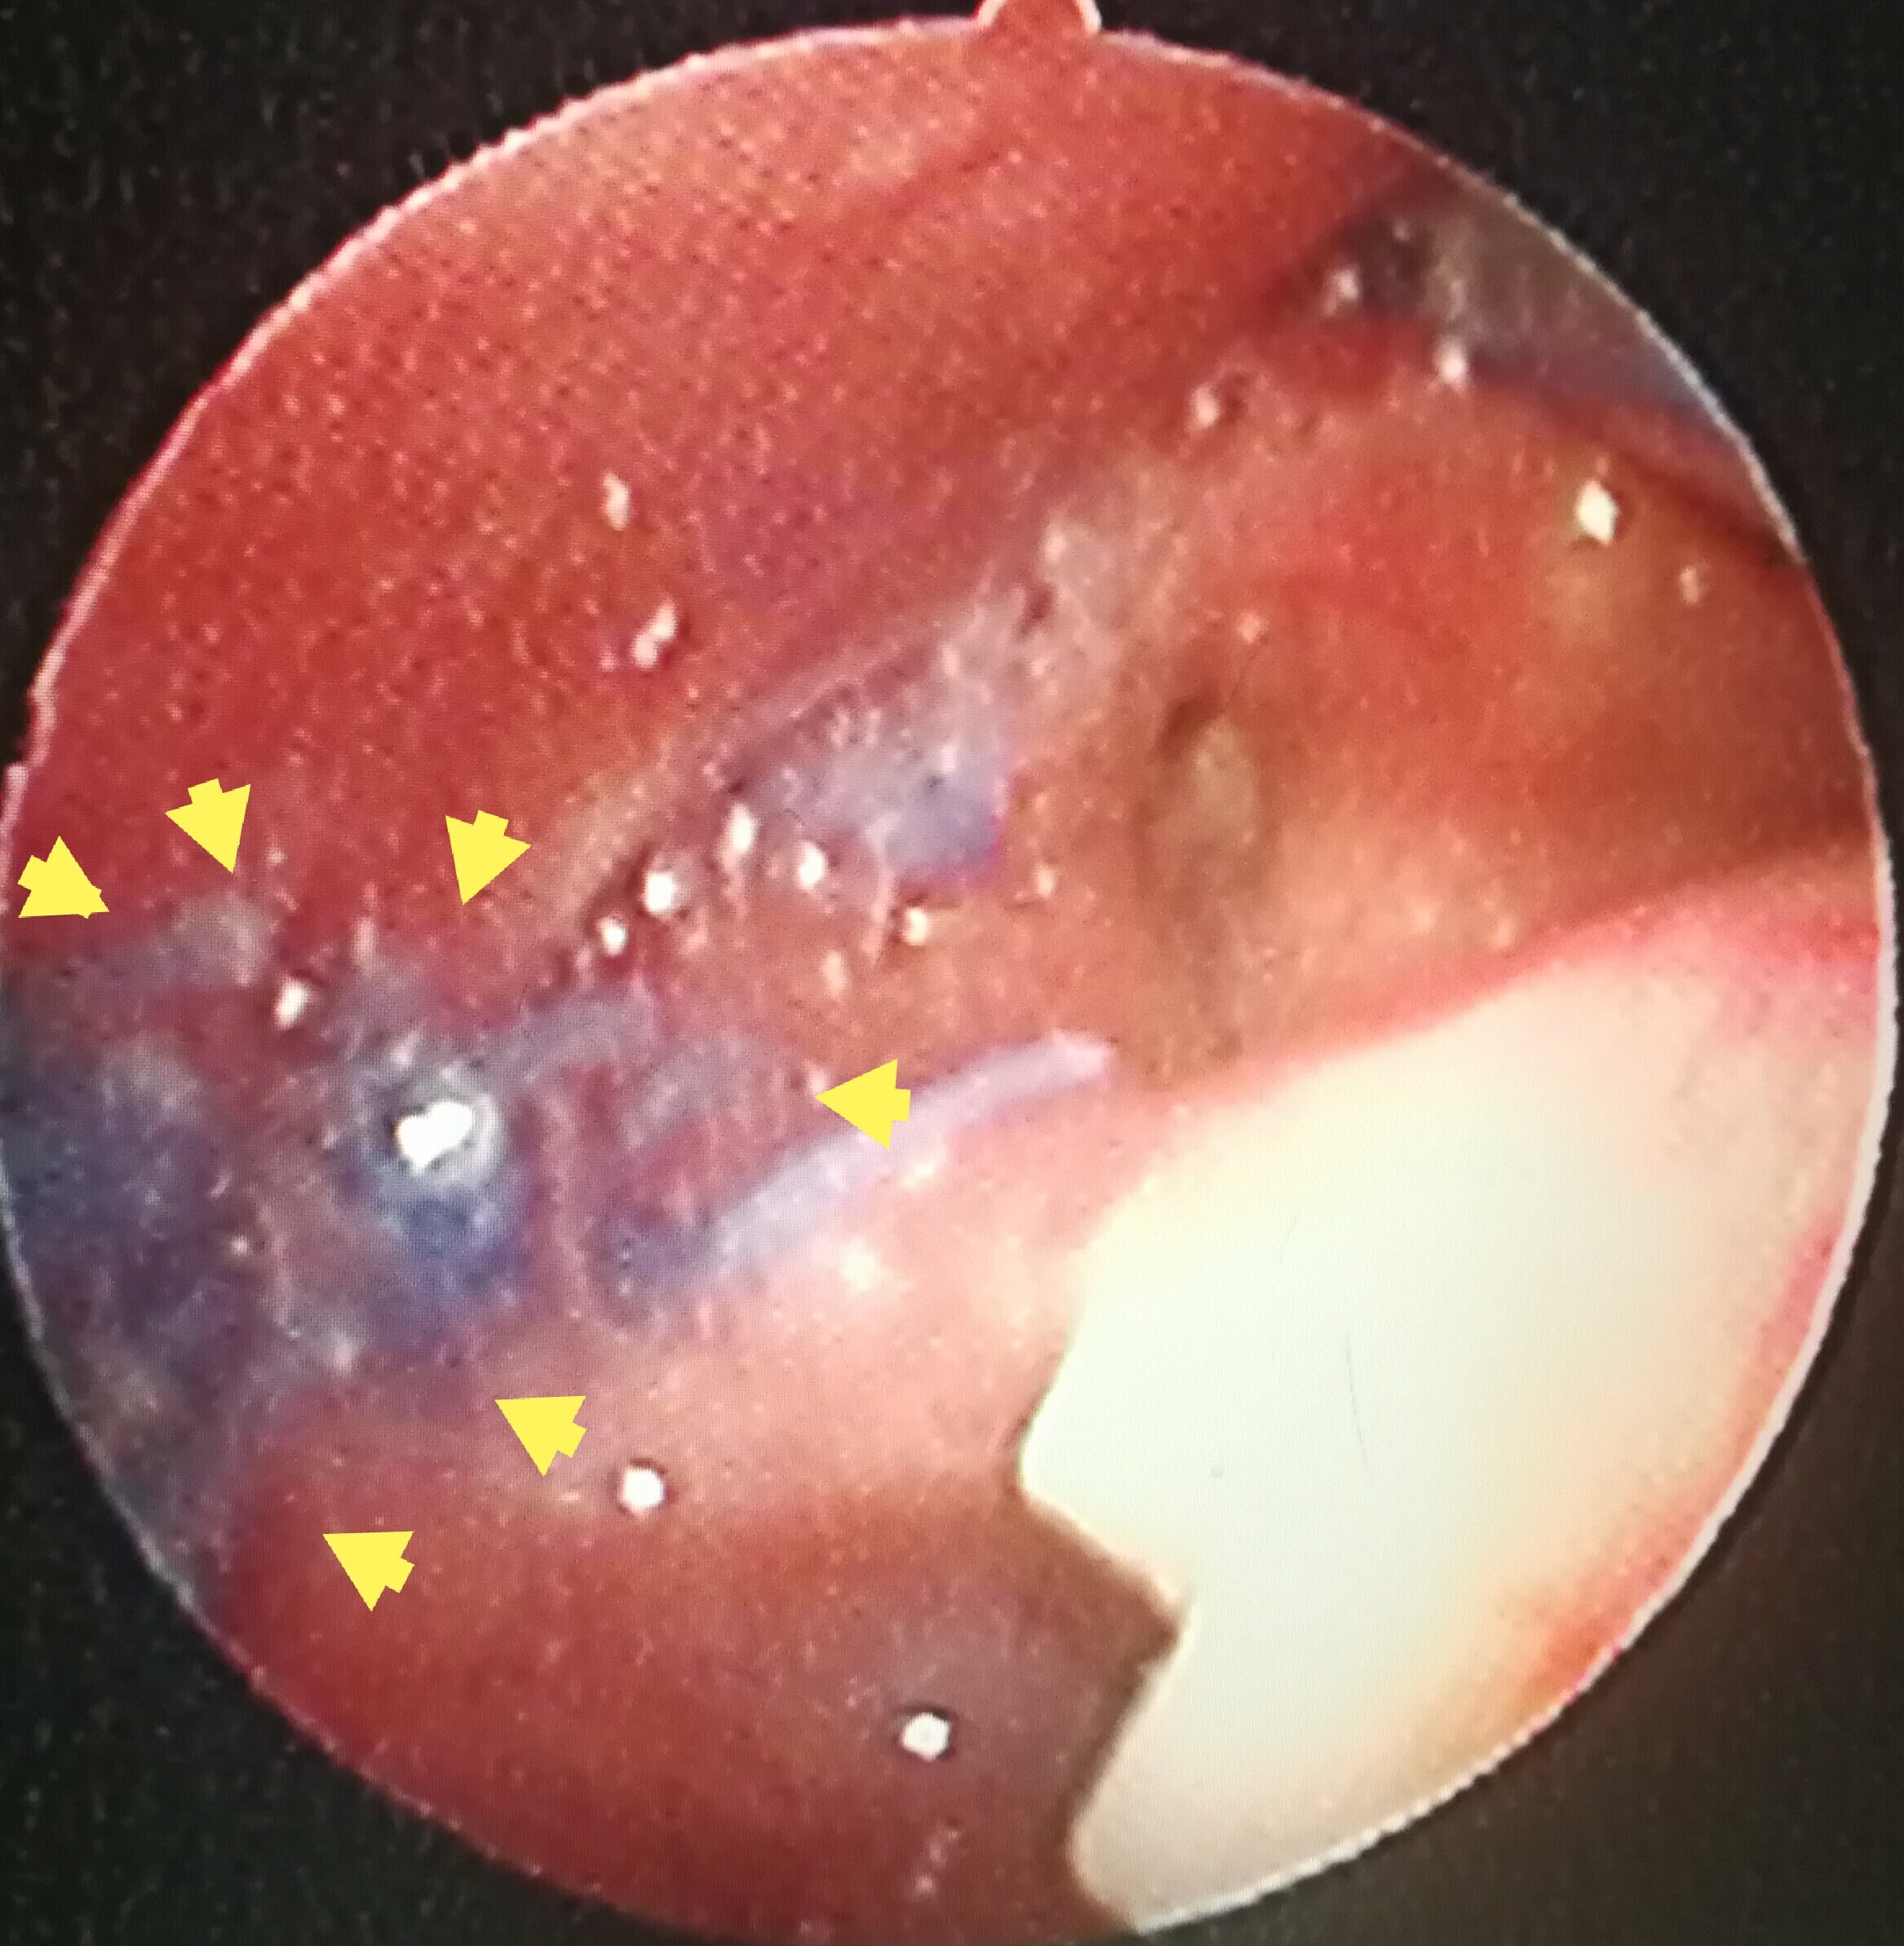

窄带成像内镜:鼻咽喉部肿瘤诊断的"照妖镜" - 好大夫在线

图片尺寸1600x1042